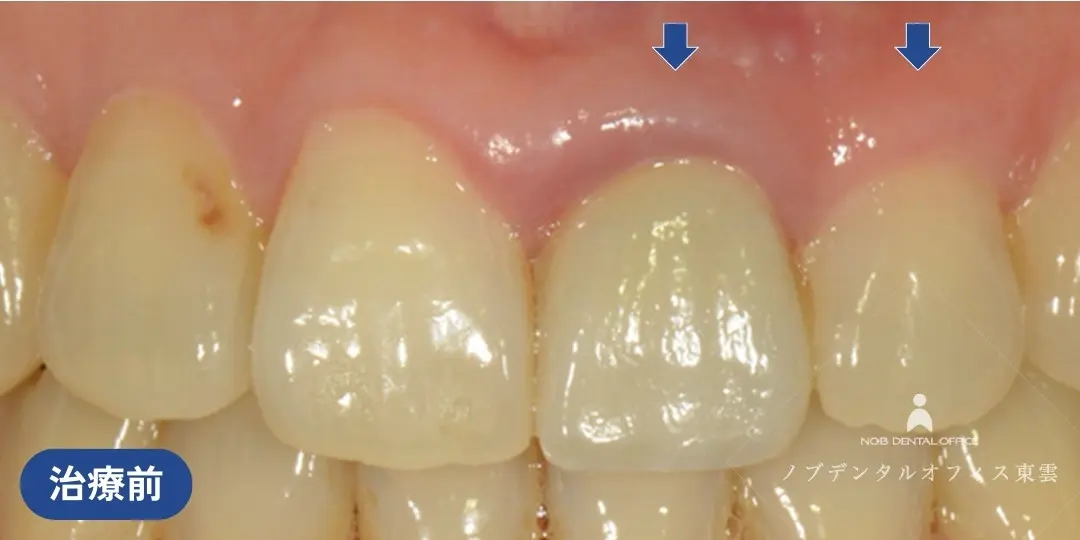

前歯の欠損を接着性ブリッジで治療した症例(60代女性)

上の前歯の歯ぐきが腫れてしまった状態を繰り返していました。

診察の結果、歯根に亀裂(きれつ)があり、残念ながら抜歯が必要との診断でした。

当院で抜歯を行いました。

インプラント・ブリッジ・入れ歯の治療計画をお話しさせていただき、治療期間やリスク、審美性や周囲の歯への負担を考慮して、接着性ブリッジで修復しました。

接着性ブリッジとは、隣の歯の一部のみを削り、貼り付けるタイプの補綴物です。

支台歯の削る量を最小限に済ませ、審美性も高いのが特徴です。

抜歯した状態。治療期間中は仮歯を入れます。

隣の歯の一部のみを削り、ジルコニアを貼り付けています。削る量が少なく負担の少ない治療です。